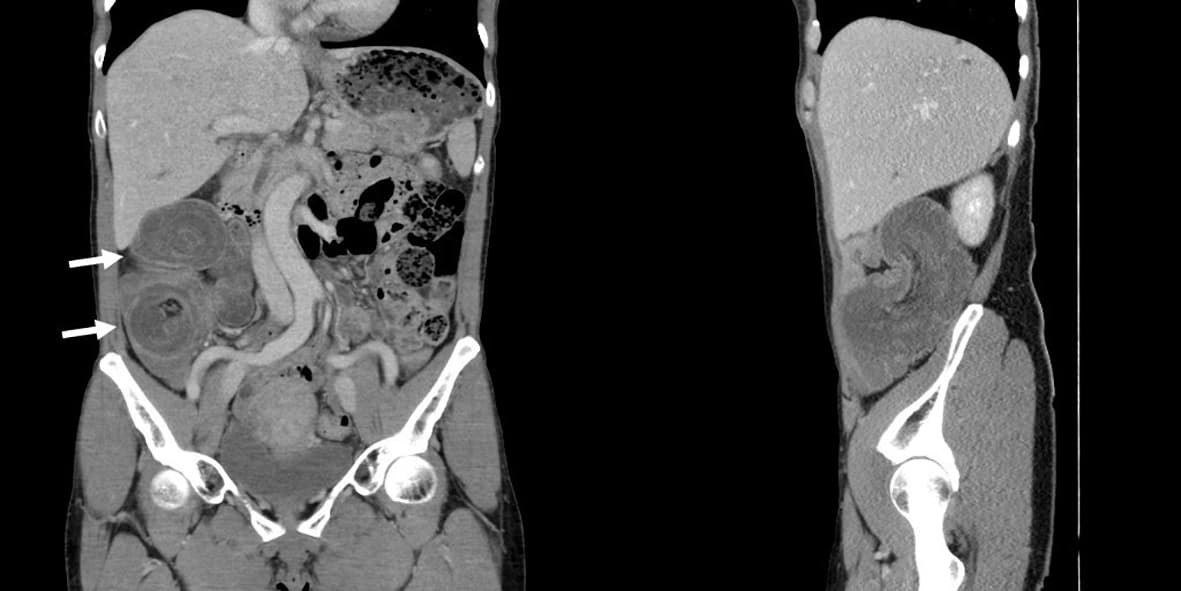

En 55-årig tidligere rask kvinde blev indlagt, da hun igennem to timer havde haft akut indsættende kraftige mavesmerter i højre hemiabdomen. Hun havde ikke kvalme, opkastninger eller diarré. Ved en objektiv undersøgelse fandt man direkte ømhed i højre hemiabdomen uden peritoneal reaktion. Der blev foretaget en CT, som viste karakteristisk skydeskivekonfiguration i højre side af abdomen, hvilket tydede på intestinal invagination [1].